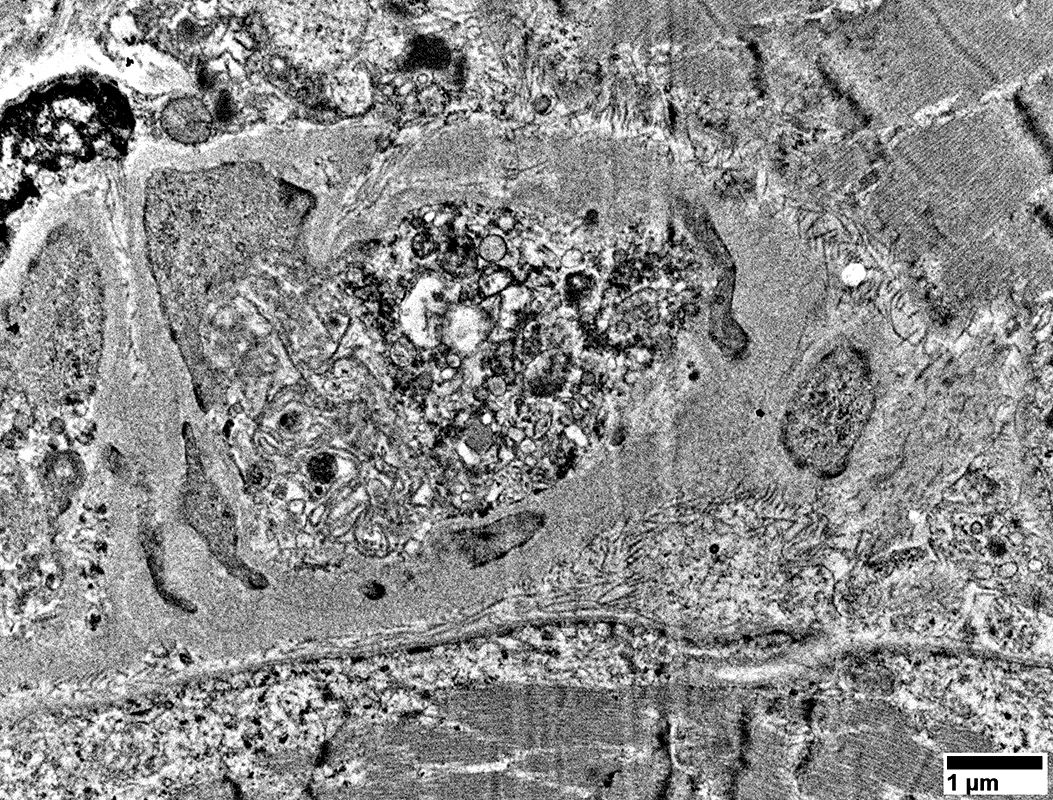

Large cells near vessels with

Mitochondrial proliferation & enlargement

Lipid droplets

From: R Schmidt